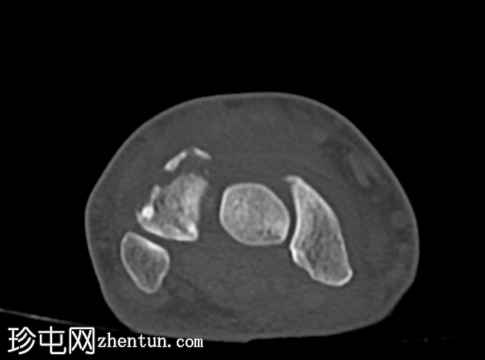

轴位片

平扫

CT轴位、矢状位和冠状位片显示三角骨背侧粉碎性撕脱性骨折。

未见其他骨折。